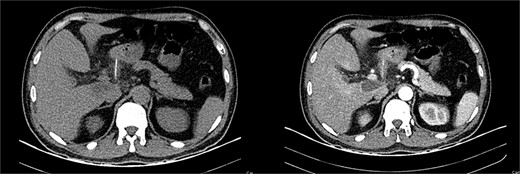

CT, the location of the fishbone in the lesser sac embedded in the pancreas.

With these findings, surgical consultation was required, and surgery was decided. On laparotomy, multiple adhesions were seen between the transverse colon and stomach. After opening the lesser sac, 1000 ml of pus was drained, and after exhausting washing with saline. A foreign body resembling a fishbone was discovered attached to the head of the pancreas and the posterior wall of the stomach and duodenum. No visible perforation was seen in the stomach or duodenum despite numerous maneuvers. With these findings, the foreign body was removed, a culture was obtained, and a drain was placed without complications. (Fig. 3).